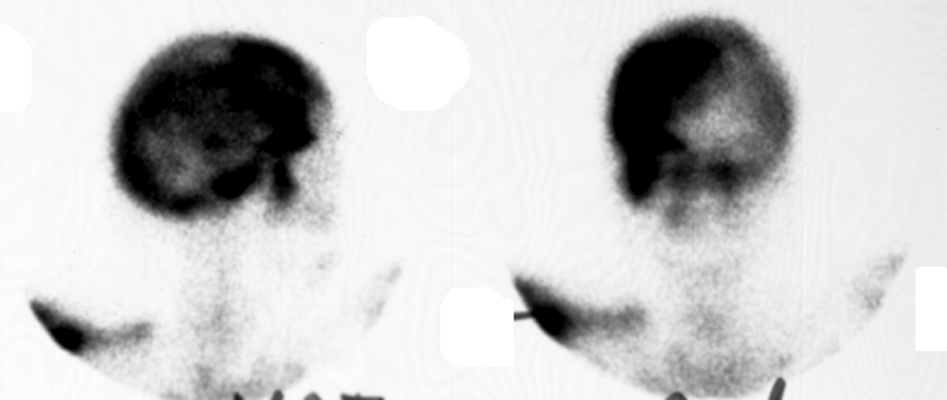

Plain film of the skull reveals a large mottled area of radiolucency with small areas of increased density within it. The MR image of the skull reveals a thickened, enlarged cranium with increase in the marrow space. Two bone scan images also reveal increased activity in the skull, more localized to one side, characteristic to the localized disease seen in Paget's. This is classic cranial involvement of Paget's. In the cranium, bone sclerosis may produce circular radiodense lesions in one area, whereas osteoporosis circumscripta is noted elsewhere. In the skull, the common region of involvement is the cranial vault. The osteolytic phase is called osteoporosis circumscripta and appears as multiple geographic, well-demarcated regions of bone resorption that may be mistaken for metastases. Focal radiodensities occur as pagetoid bone is formed. In the quiescent phase, there is a radiodense cotton-wool appearance with a thickened vault.

Lateral skull - Click on the image for a larger versionAMRI skull - Click on the image for a larger versionBBone scan skull - Click on the image for a larger versionC